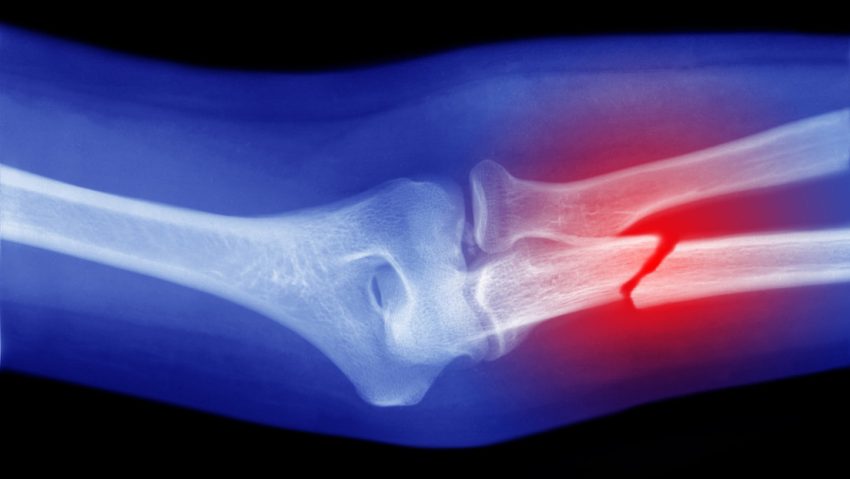

Células capaces de ‘convertirse en hueso’ podrían ser la clave para curar fracturas graves

Científicos de la Facultad de Medicina Perelman de la Universidad de Pensilvania (EE.UU.) ha hecho un descubrimiento que podría facilitar la curación de fracturas, principalmente aquellas más complicadas.

En modelos con ratones, los investigadores, liderados por el doctor Ling Qin, demostraron que un tipo de célula madre que se ha descubierto recientemente es capaz de transformarse en células óseas y conducir a una eficaz curación.

Descubrieron que, tras una lesión ósea, migran al callo de fractura (estructura temporal que se forma para guiar la curación) y allí se transforman en células óseas.

De este modo, las Prg4+ podrían ser la clave para la curación ósea tras fracturas graves, cuando el hueso y la piel se rompen y se produce una pérdida extrema de tejido.